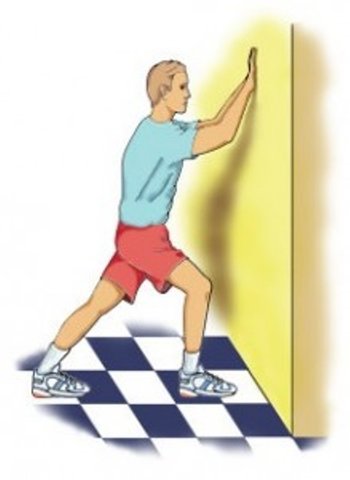

-انجام حرکات کششی: کشش عضلات ساق و کف پا که حرکات را سه با در روز(صبح ها پیش از برداشتن اولین گام و قبل از ایستادن و پس از نشستن طولانی)

الف)کشش عضلات ساق پا:

2-روبه دیوار به فاصله یک گام ایستاده ،کف دستها را به دیوار چسبانده و پایی را که دچار عارضه است به عقب بکشید تا جایی که پاشنه پا از زمین بلند نشود.